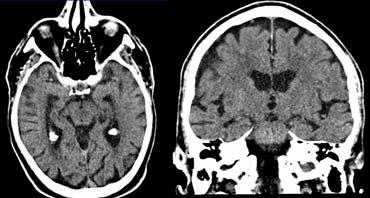

Các hình ảnh cho thấy bệnh nhân có nhồi máu PCA chiến lược liên quan đến hồi hải mã.

Loại nhồi máu này có thể dẫn đến sa sút trí tuệ đột ngột nếu nằm ở bán cầu ưu thế.

Thường sẽ không dẫn đến sa sút trí tuệ nếu xảy ra ở bán cầu không ưu thế.

Ở hầu hết bệnh nhân VaD, có bệnh lý chất trắng lan tỏa với các tổn thương hợp lưu lớn (Fazekas 3).

Ở một số bệnh nhân này, não thất có thể giãn do teo não toàn thể và một số cũng có teo thùy thái dương trong.

Các hình ảnh là của một bệnh nhân mắc VaD, nhưng thùy thái dương trong bình thường.